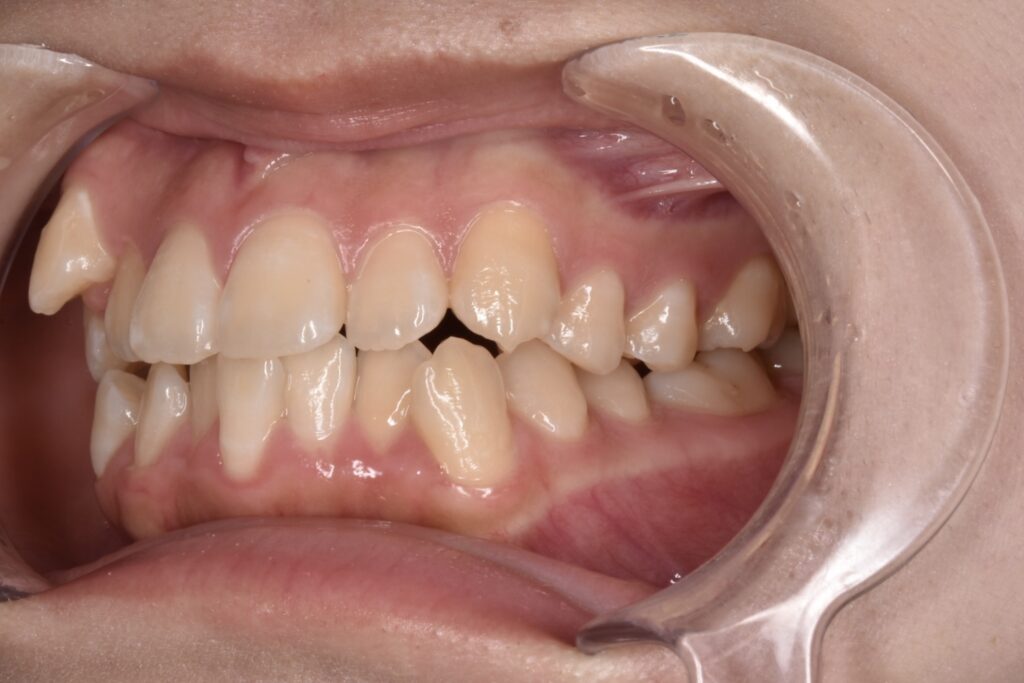

10代女性 以前より八重歯をなくしたいと悩んでいて、高校卒業と同時に矯正を始めたいと、ご家族でご相談にご来院くださいました。

Before

現在矯正開始から38週経過し38枚目になっています。追加アライナーなし、順調に経過しています。八重歯感もだいぶ改善してきましたね。噛み合わせは本人様は全然気にならない様ですが最後に調整していきます。追加アライナーとゴムかけなどです。